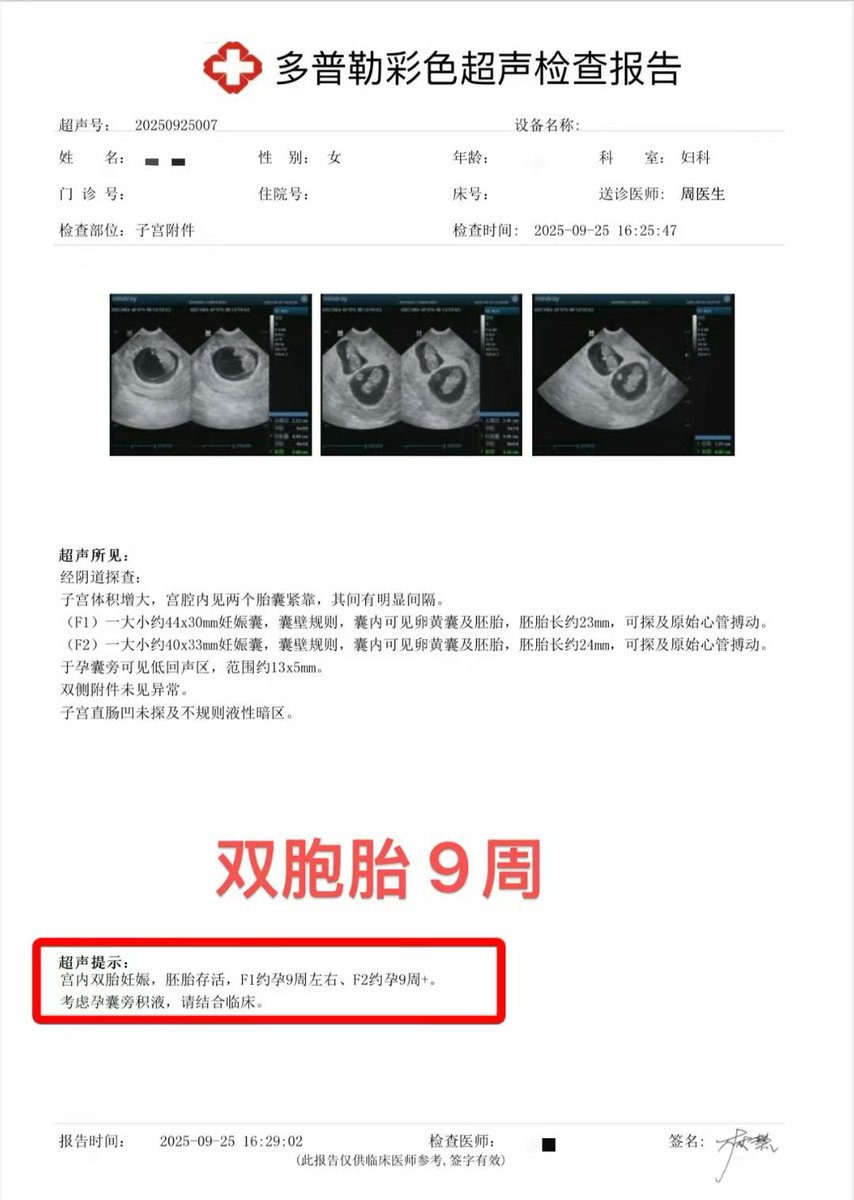

![代孕.HIV.洗精.国内代孕机构 (@wangjb168) on Twitter photo 【幸福奶爸的日常✨】

[庆祝]有了璨璨宝宝后,#男宝宝 生活就像加糖了🍼哄奶能技✅|洗澡手法|✅儿保按摩✅|阳光补✅钙

(偷偷夸自:己育儿知识学不少) 称职#奶爸 咨询微信:a18025307951

#失独代孕 #洗精代孕 #三代包成功 #选性别代孕 #夫妻代孕

#试管婴儿 #试管助孕 #代孕 #广州代孕 【幸福奶爸的日常✨】

[庆祝]有了璨璨宝宝后,#男宝宝 生活就像加糖了🍼哄奶能技✅|洗澡手法|✅儿保按摩✅|阳光补✅钙

(偷偷夸自:己育儿知识学不少) 称职#奶爸 咨询微信:a18025307951

#失独代孕 #洗精代孕 #三代包成功 #选性别代孕 #夫妻代孕

#试管婴儿 #试管助孕 #代孕 #广州代孕](https://pbs.twimg.com/media/GwxaTC3aoAASBa5.jpg)